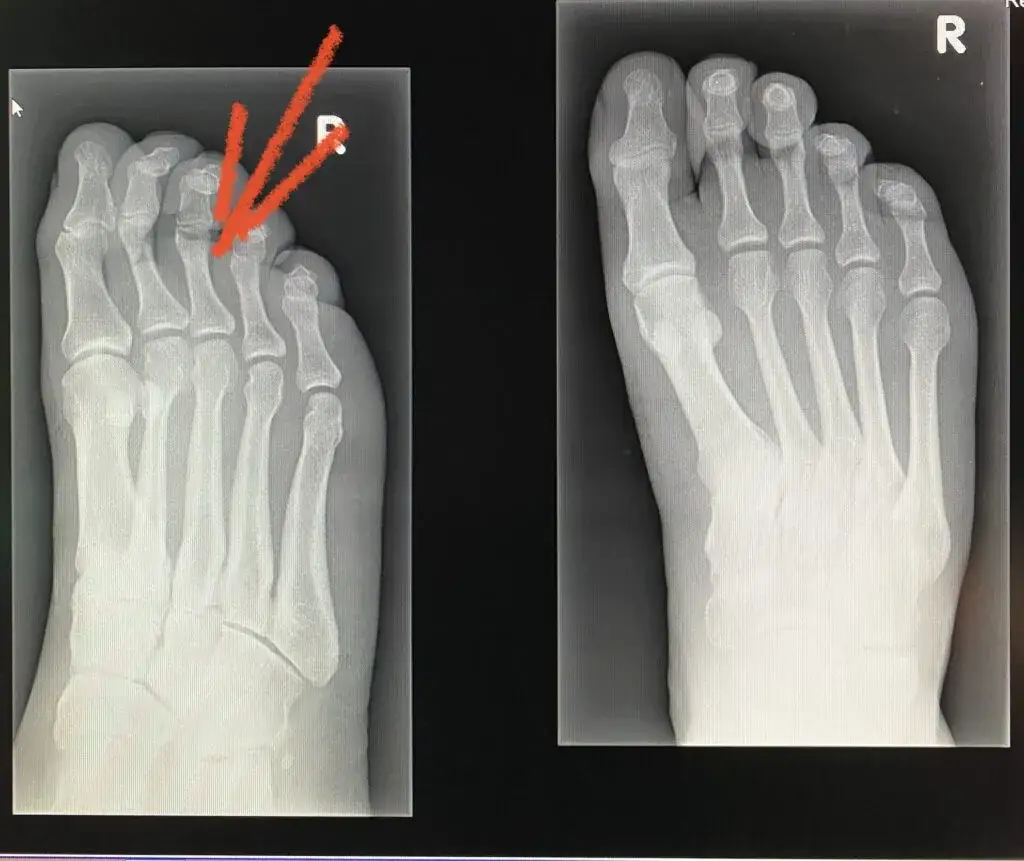

Diagnostyka obrazowa (RTG, USG, Rezonans): Kto zleca i interpretuje wyniki?

W przypadku problemów z narządem ruchu, często niezbędne jest "zajrzenie do środka", aby postawić precyzyjną diagnozę. To właśnie ortopeda jest głównym specjalistą, który zleca i interpretuje badania obrazowe, takie jak RTG (rentgen), USG (ultrasonografia), MRI (rezonans magnetyczny) czy TK (tomografia komputerowa). Dzięki tym badaniom może ocenić stan kości, chrząstek, więzadeł, ścięgien i mięśni, wykryć złamania, zmiany zwyrodnieniowe, guzy czy stany zapalne. Bez jego wiedzy i doświadczenia, prawidłowa interpretacja tych skomplikowanych obrazów byłaby niemożliwa.